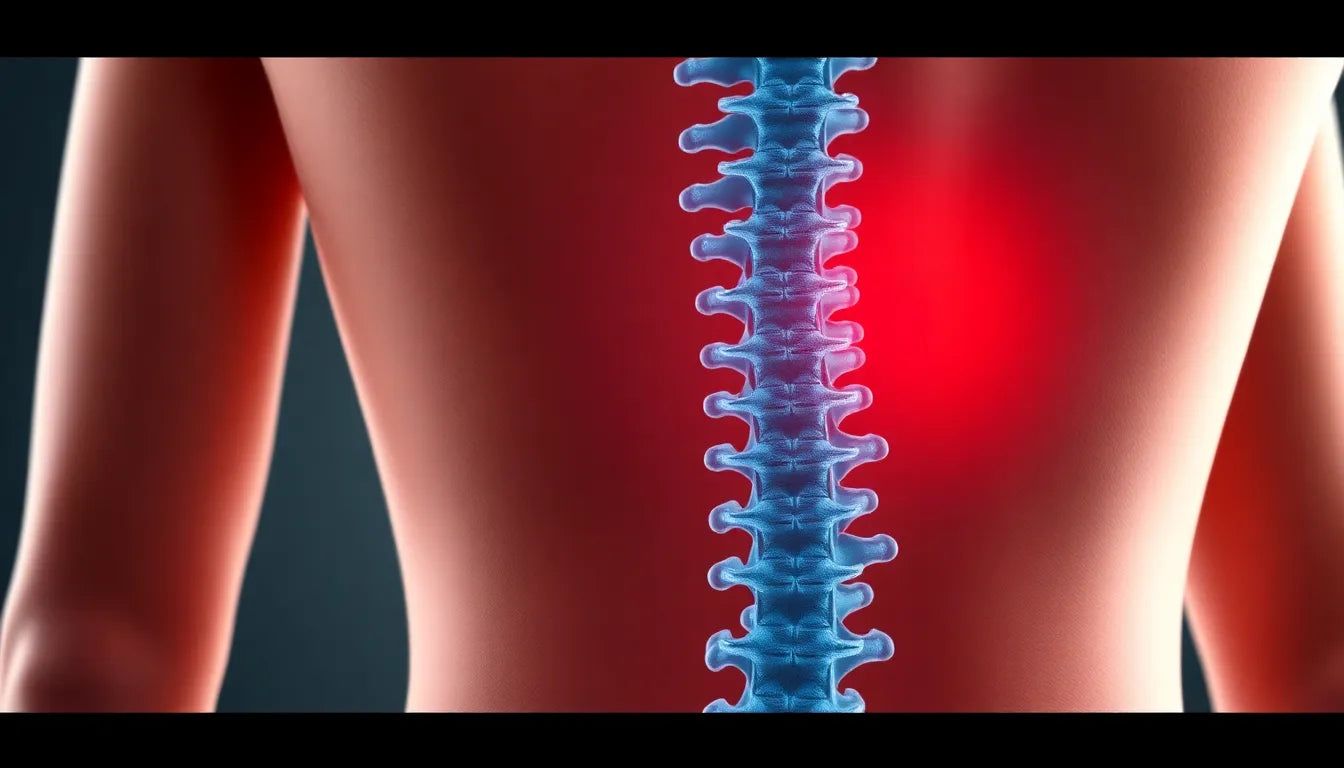

Soulagez votre dos : dites adieu à la douleur de la hernie discale

Le mal de dos, souvent causé par une hernie discale, peut sérieusement affecter la vie quotidienne. Comprendre ses causes, comme la pression excessive ou une mauvaise posture, est crucial. Un diagn...

Soulagez la spondylose de votre chat avec des soins adaptés et un environnement confortable

La spondylose chez le chat est une affection dégénérative de la colonne vertébrale qui impacte leur qualité de vie. Reconnaître les symptômes précocement, comme la raideur et la douleur, est crucia...